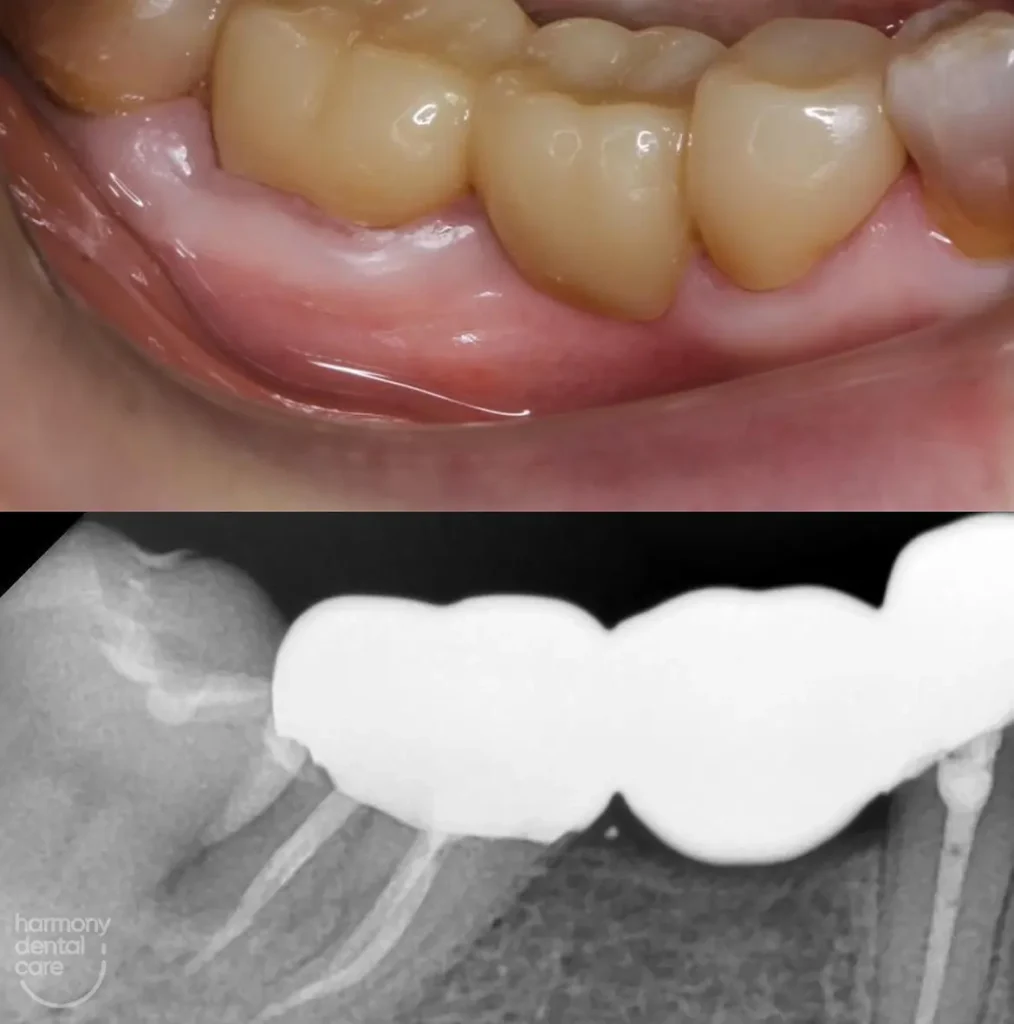

Gusi bengkak sering kali jadi masalah yang bikin kita merasa tidak nyaman, baik itu saat makan, menyikat gigi, atau bahkan